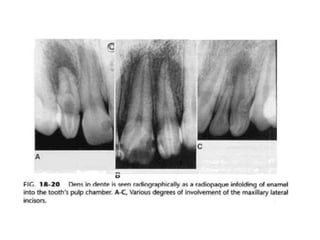

11. Dens Invaginatus, Dens In Dente

Merupakan hasil dari invaginasi permukaan

enamel ke bagian dalam dari gigi.